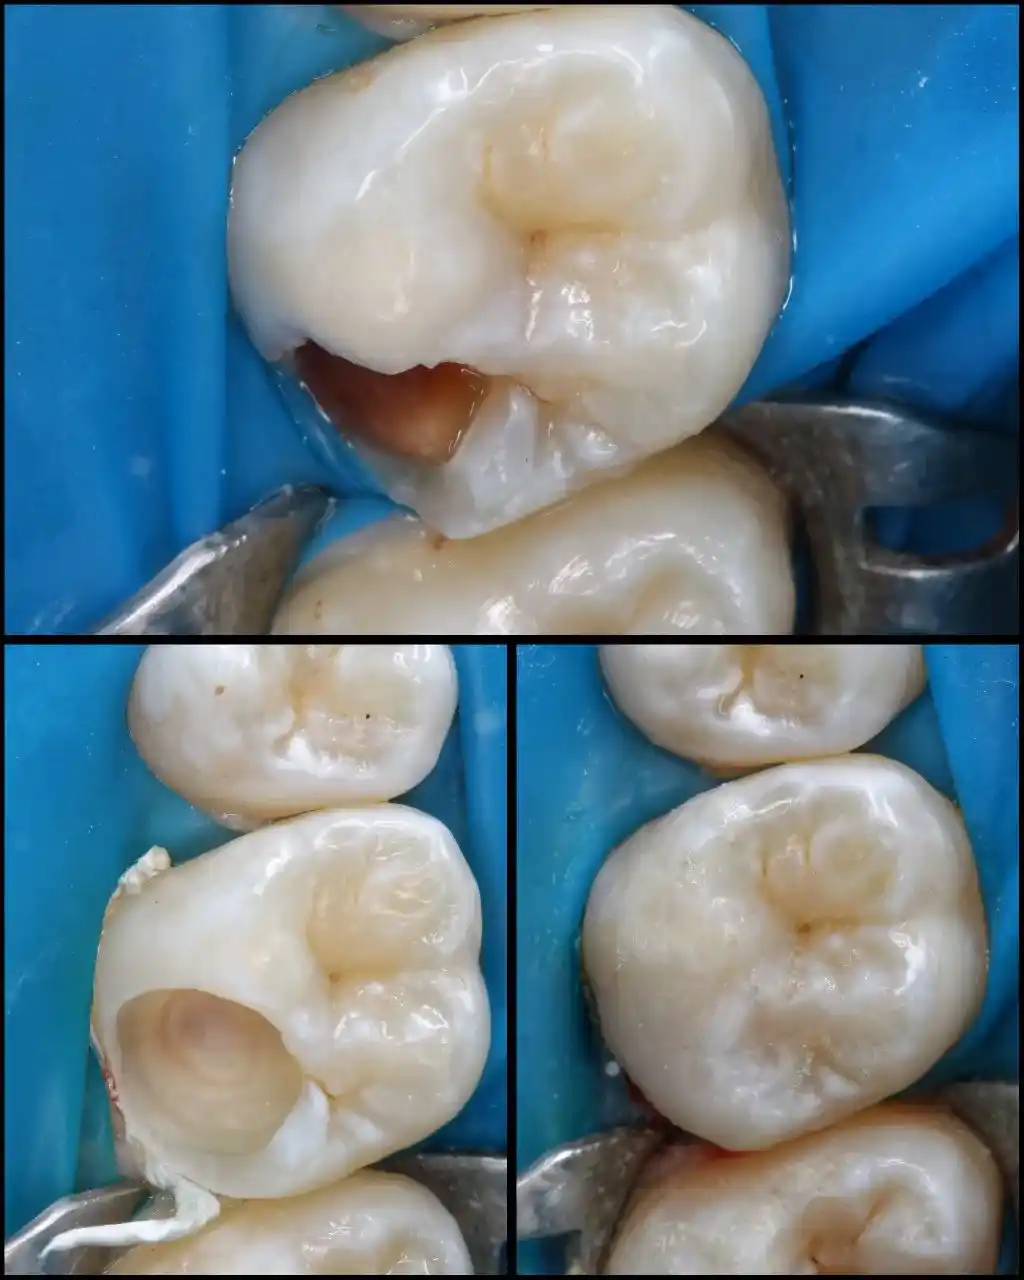

Наші роботи "лікування зубів вдома"

Лікування карієсу вдома.

Лікування зубів вдома при карієсі включає видалення пошкоджених тканин та встановлення фотополімерних пломб з ізоляцією зубів системою кофердам. Сучасні матеріали та портативне обладнання гарантують високу якість реставрації та довговічність результату. Усі процедури проходять із дотриманням суворих санітарних норм.